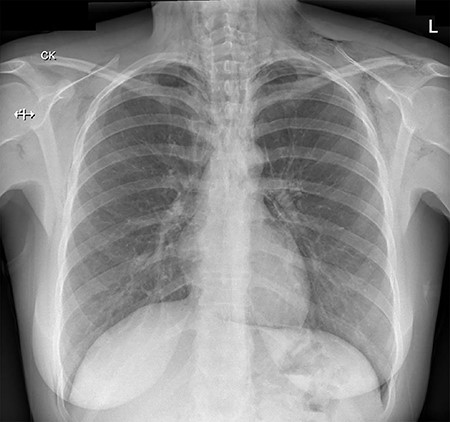

On initial assessment, pneumoderma was palpable on the anterior chest wall and neck. Blood tests revealed a haemoglobin level of 176 g/L (normal range 110–150 g/L) and white blood cell count of 17.71 × 109/L (normal range 3.5–11 × 109/L). Serum urea and creatinine were mildly raised from her baseline. The C-reactive protein level was 7 mg/L (normal range < 5 mg/L). These results were largely explained by dehydration secondary to prolonged vomiting. A chest radiograph (Fig. 1) revealed extensive surgical emphysema and pneumomediastinum.

A chest radiograph illustrating surgical emphysema and pneumomediastinum.